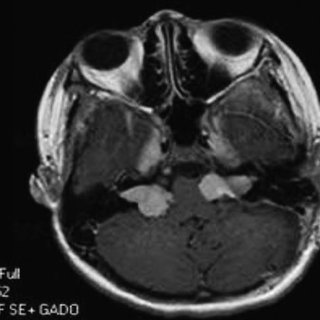

诊断前庭神经鞘瘤的金标准无疑是钆增强磁共振成像(MRI),但一些检查可能会引起前庭神经鞘瘤的怀疑。

扫描和测试的进步使得识别小型听神经瘤(仍局限于内耳道)成为可能。磁共振成像使用钆作为增强对比材料是识别听神经瘤的优选诊断测试。如果存在听神经瘤,所形成的图像清楚地定义了它,并且这种技术可以识别直径小至5毫米(扫描间隔)的肿瘤。

当磁共振成像不可用或无法进行时,建议对怀疑有听神经瘤的患者进行计算机断层扫描(CT扫描),并进行对比。计算机断层扫描和听力图的结合提高了磁共振诊断听神经瘤的可靠性。